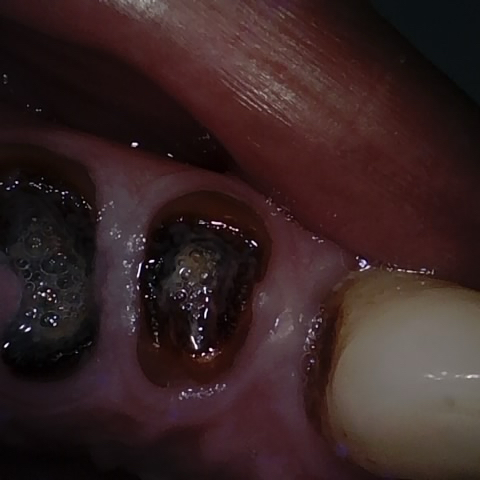

Annotated as "Good"